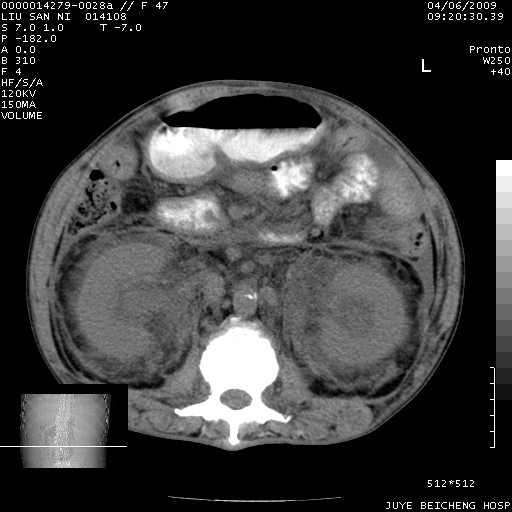

以下是引用前行在2009-4-7 10:31:00的发言:[br]肝脾肿大;双肾增大,双肾盂少量积水可能,肾膜膜增厚,肾周间隙增宽,并见桥间隔,提示结缔组系统疾病、系统性红瘢狼疮肾可能性大。继发右侧胸腔、心包、腹腔积液。

以下是引用深泽交通医院在2009-4-7 11:21:00的发言:[br]双侧肾周密度增高,见条索影,右肾实质见点片状低密度区,考虑弥漫肾炎【自身免疫性?】;;肾性水肿征